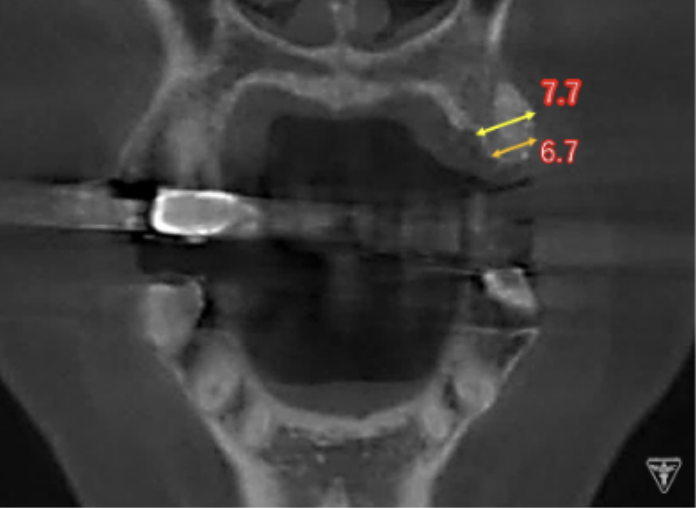

インプラント埋入前のCTによる確認